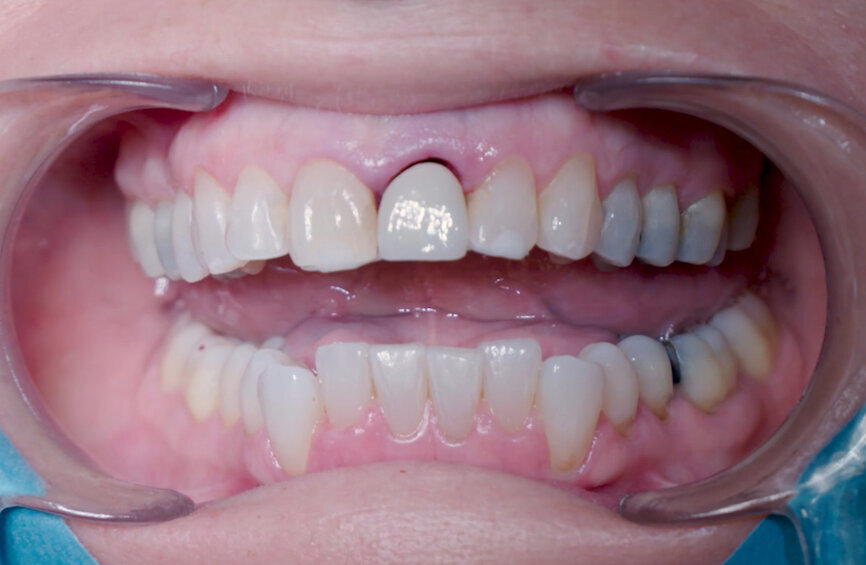

A 53-year-old female patient presented to the office with a fractured left central incisor which had been repeatedly bonded to a ceramic crown (Figs. 1 & 2). Anamneses and examination established good systemic and oral health, a well-balanced occlusion and no smoking habits. Cone beam computed tomography (CBCT) and a periapical radiograph showed external root resorption with very limited insertion into the alveolar bone, insufficient for adequate conventional intra-radicular post placement (Figs. 3 & 4). Considering that the fractured tooth was in the aesthetic zone, the patient requested restoration in the safest and fastest way possible.

Fig. 1: Initial situation, extra-oral view.

Fig. 2: Initial situation, intra-oral view.